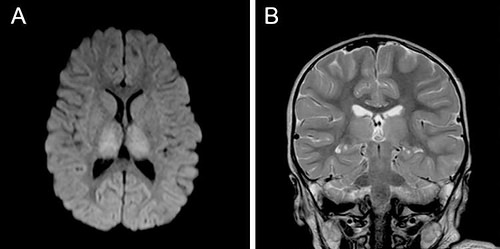

治疗在溺水后大约162天结束,核磁共振扫描显示,Eden的大脑依然有轻度的残留损伤,但经历了近乎完全逆转的皮质和白质萎缩。